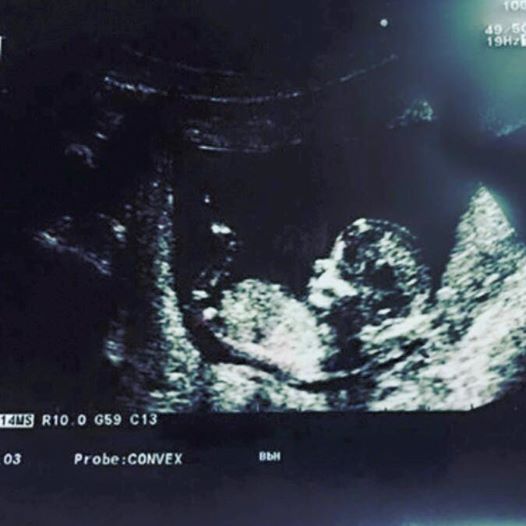

“Kjo esht goca (engjelli im) qe sod mbushi 7 Muaj , me shkenc do mund te lind dhe ne muaj 7 si shum te tjer , po ne fund tetorit do lindje ne muaj 9 e shendosht e bukur si nje princesh sipas te dhenav te doktorrit ku esht kontrolluar vazhdimisht te Dr (Agroni ne prishtine) . Po per fat t’keq nuk arriti te lind pasi ne menyr padrejt u mbyt nga nena e saj Kristela Gjoka dhe njerzt e saj qe e rrethojn pa dijenin time . Mua me vjen keq qe nuk arrita te kem ne krahror gocen time pasi isha njohur dhe me te duke degjuar un rrahjet e zemres saj ,